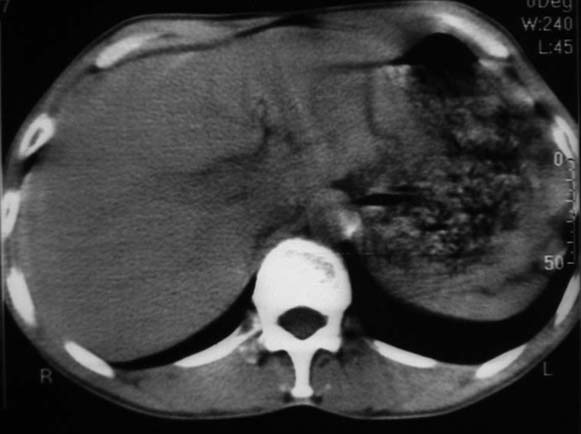

男,50y,右上腹包块痛10天,查:右上腹饱满,右肋下触及6*6cm大小包块,质硬,压痛。患者诉:10天前感冒胸闷,痛,后痛及右上腹部,既往有肝炎病史。

没有增强!只能考虑左叶内侧段巨块型肝癌(外生型)可能性大;胆囊呢?不除外胆囊癌累及肝脏。

我倒是先考虑胆囊癌(肿块型)肝脏受侵可能性大,做个c+

病变位于胆囊窝内,其内密度不均,肝总管及胆总管扩张,胃里面没有清水充盈,不解为什么楼主不做好了准备再做呢,支持:“左叶内侧段巨块型肝癌(外生型)可能性大;不除外胆囊癌累及肝脏”建议增强吧。

考虑:肝左内叶巨块型癌,主动脉旁淋巴结转移.(有一层面似见胆囊受压.)